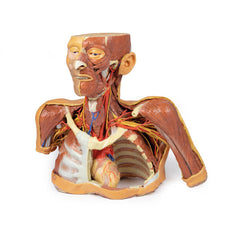

3D Printed Head and Visceral Column of the Neck

The face: On the right side of the head the parotid gland has been removed to reveal the facial nerve and all its branches (temporal, zygomatic, buccal, marginal mandibular and cervical) and demonstrate the spatial relations of structures embedded in the gland from superficial to deep (facial nerve, retromandibular vein, external carotid artery). In the surrounding region the temporalis, masseter and posterior belly of digastric are exposed, as are and the facial artery, transverse facial artery and superficial temporal artery. The facial vein and transverse facial vein are clearly visible uniting to form the common facial vein which is joined by the retromandibular vein to form the external jugular vein.

Viewed from the anterior aspect the face has been dissected to display some of the facial muscles around the mouth (buccinator [on the left], orbicularis oris and zygomaticus major). On the left side of the infratemporal fossa has been open to expose the medial and lateral pterygoids.

The lateral pterygoid is divided to show the mandibular division of the trigeminal nerve dividing into the lingual nerve and the inferior alveolar branch. Also on the left side the branches of the ophthalmic division of the trigeminal that supply the skin above the eyebrows and scalp (supraorbital [left only] and supratrochlear nerves [both sides]) are dissected. The submandibular gland is clearly visible below the mandible on both sides as are the facial arteries and veins as they course over the mandible.

The neck: The musculoskeletal portion of the neck have been removed to display the pharynx posteriorly, the larynx anteriorly, and the neurovascular bundles laterally. The suprahyoid and infrahyoid muscles can be seen on the neck, as well as the cricothyroid muscle.

When looking up the length of the trachea from below, the vocal folds are visible. The hypoglossal nerve can be seen winding around the lateral surface of the external carotid artery and the external branch of superior laryngeal nerve is seen descending in the neck. The internal jugular vein, the common carotid artery and its bifurcation into external and internal carotid arteries are clearly seen on both left and right. The vagus nerve in the carotid sheath is also visible. The ansa cervicalis is visible emerging below the digastric muscle and descending on the surface of the internal jugular vein. The internal branch of the superior laryngeal nerve can be seen below the superior thyroid artery on the left. The superior thyroid artery branching from the external carotid artery is seen descending in the anterior neck. The internal branch of the superior laryngeal artery is visible on the left piercing the thyrohyoid membrane above the inferior constrictor where this muscle is attached to the hyoid bone.

Posterior view of the pharynx: The superior, middle and inferior pharyngeal constrictors are indicated on the pharynx wall. The oesophagus can be identified emerging from the lower end of the pharynx. The posterior horn of the hyoid bone acts as a useful landmark. The carotid sheath seen from behind clearly shows the vagus nerve and its pharyngeal branches on the left. The recurrent laryngeal nerve is briefly visible on the left lying medial to the inferior thyroid artery. The occipital arteries are visible as they curve around the mastoid process. The vertebral arteries are seen either side of the brainstem as they enter the foramen magnum. The cerebellum has been removed to allow the fourth ventricle to be exposed. The cut surfaces of the cerebellar peduncles are clearly visible. A large portion of the posterior inferior cerebellar artery on the right is still visible as it winds around around the brainstem.

Cranial Cavity: The left and right orbits have been opened to reveal the orbital nerves and vessels along with the eyes and optic nerves. The optic chiasm, optic tracts and the lateral geniculate bodies are retained thus showing a large part of the visual pathways. The brainstem is cut at the level of the superior colliculi on the left and slightly lower on the right. The olfactory tracts and bulbs are also demonstrated. The origins of many of the cranial nerves from the brainstem are clearly visible.

3D Printed Head and Visceral Column of the Neck

This 3D print specimen preserves a series of features of the head and visceral column of the neck:The face: On the right side of the head the parotid gland has been removed to reveal the facial nerve and all its branches (temporal, zygomatic, buccal, marginal mandibular and cervical) and demonstrate the spatial relations of structures embedded in the gland from superficial to deep (facial nerve, retromandibular vein, external carotid artery). In the surrounding region the temporalis, masseter and posterior belly of digastric are exposed, as are and the facial artery, transverse facial artery and superficial temporal artery. The facial vein and transverse facial vein are clearly visible uniting to form the common facial vein which is joined by the retromandibular vein to form the external jugular vein.

Viewed from the anterior aspect the face has been dissected to display some of the facial muscles around the mouth (buccinator [on the left], orbicularis oris and zygomaticus major). On the left side of the infratemporal fossa has been open to expose the medial and lateral pterygoids.

The lateral pterygoid is divided to show the mandibular division of the trigeminal nerve dividing into the lingual nerve and the inferior alveolar branch. Also on the left side the branches of the ophthalmic division of the trigeminal that supply the skin above the eyebrows and scalp (supraorbital [left only] and supratrochlear nerves [both sides]) are dissected. The submandibular gland is clearly visible below the mandible on both sides as are the facial arteries and veins as they course over the mandible.

The neck: The musculoskeletal portion of the neck have been removed to display the pharynx posteriorly, the larynx anteriorly, and the neurovascular bundles laterally. The suprahyoid and infrahyoid muscles can be seen on the neck, as well as the cricothyroid muscle.

When looking up the length of the trachea from below, the vocal folds are visible. The hypoglossal nerve can be seen winding around the lateral surface of the external carotid artery and the external branch of superior laryngeal nerve is seen descending in the neck. The internal jugular vein, the common carotid artery and its bifurcation into external and internal carotid arteries are clearly seen on both left and right. The vagus nerve in the carotid sheath is also visible. The ansa cervicalis is visible emerging below the digastric muscle and descending on the surface of the internal jugular vein. The internal branch of the superior laryngeal nerve can be seen below the superior thyroid artery on the left. The superior thyroid artery branching from the external carotid artery is seen descending in the anterior neck. The internal branch of the superior laryngeal artery is visible on the left piercing the thyrohyoid membrane above the inferior constrictor where this muscle is attached to the hyoid bone.

Posterior view of the pharynx: The superior, middle and inferior pharyngeal constrictors are indicated on the pharynx wall. The oesophagus can be identified emerging from the lower end of the pharynx. The posterior horn of the hyoid bone acts as a useful landmark. The carotid sheath seen from behind clearly shows the vagus nerve and its pharyngeal branches on the left. The recurrent laryngeal nerve is briefly visible on the left lying medial to the inferior thyroid artery. The occipital arteries are visible as they curve around the mastoid process. The vertebral arteries are seen either side of the brainstem as they enter the foramen magnum. The cerebellum has been removed to allow the fourth ventricle to be exposed. The cut surfaces of the cerebellar peduncles are clearly visible. A large portion of the posterior inferior cerebellar artery on the right is still visible as it winds around around the brainstem.

Cranial Cavity: The left and right orbits have been opened to reveal the orbital nerves and vessels along with the eyes and optic nerves. The optic chiasm, optic tracts and the lateral geniculate bodies are retained thus showing a large part of the visual pathways. The brainstem is cut at the level of the superior colliculi on the left and slightly lower on the right. The olfactory tracts and bulbs are also demonstrated. The origins of many of the cranial nerves from the brainstem are clearly visible.